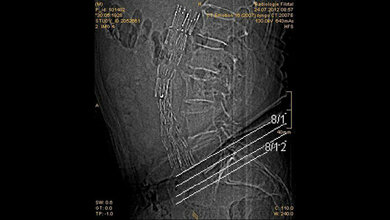

Das Screening erfolgt per Ultraschalluntersuchung. Wird dort festgestellt, dass die Bauchschlagader gefährlich erweitert ist, kann schnell gehandelt werden. Dabei kann etwa operativ ein Ersatzgefäß in den erkrankten Bereich der Schlagader eingenäht werden. Eine schonende Alternative dazu stellt das minimal-invasive Einbringen einer Stentprothese über einen kleinen Leistenschnitt dar. Hierbei wird die Gefäßprothese unter Röntgenkontrolle exakt an die erforderliche Stelle geschoben und dort entfaltet. Auf eine große Operation kann so verzichtet werden.